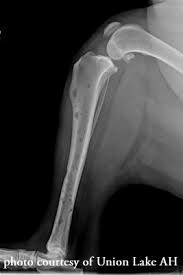

Or a dramatic, sudden fracture. In dogs, bone cancer also can occur as a primary or metastatic disease, but in contrast to humans, the most common form of bone cancer seen in dogs in the u.s. Tumors can begin either directly in the affected bone, or cancer cells can spread by a process known as metastasis, from other sites. Osteosarcoma is the most common primary bone tumor of dogs and nearly 10,000 dogs are diagnosed with this cancer each year. Here are the best ways to manage your dog's osteoarthritis.

No Bones About It Osteosarcoma Is A Bad Bone Cancer Creature Comfort Care Llc from images.squarespace-cdn.com Trouble is, bone cancer symptoms can mimic those of other, more common conditions, including arthritis, fractures and other acute skeletal injuries, and benign bone tumors. Or a small lump on the leg that becomes tender to the touch. Arthritis and cancer are two processes that can lead to severe, unremitting pain that worsens over time. It is important to remember that dogs and cats are stoic and particularly good at hiding their pain. Bone broths contain essential minerals in forms that your pet's body can easily absorb. Identifying whether your aches and pains are indicative of a nonmalignant skeletal condition or symptoms of bone cancer may potentially mean the difference between life and. Surprisingly, joint issues are common in dogs of all breeds and ages. Chondrosarcoma is a malignant form of bone cancer in dogs characterized by a tumor of neoplastic chondroid and fibrillar matrix forming in cartilage.

In dogs, bone cancer also can occur as a primary or metastatic disease, but in contrast to humans, the most common form of bone cancer seen in dogs in the u.s. I thought for sure it was just arthritis or a sprain, so i couldn't believe it when the vet told me it was bone cancer. Osteosarcoma is the most common primary bone tumor of dogs and nearly 10,000 dogs are diagnosed with this cancer each year. Arthritis and cancer are two processes that can lead to severe, unremitting pain that worsens over time. Dogs over 66 lbs are 60 times more likely to get osteosarcoma than dogs under 22 lbs.